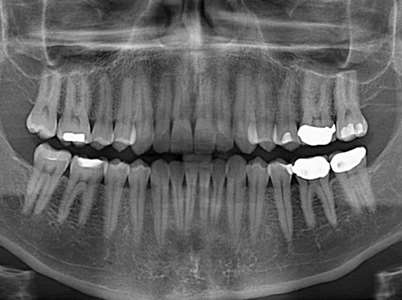

وی در ادامه به رادیوگرافی پانورامیک اشاره کرد و گفت: رادیوگرافی پانورامیک نمایی گسترده از فکین، مفصل گیجگاهی–فکی، سینوس ماگزیلا و وضعیت کلی دندان‌ها ارائه می‌دهد و برای ارزیابی دندان‌های نهفته یا نیمه‌نهفته، بررسی کیست‌ها و تومورهای فکی، تشخیص شکستگی‌ها و ارزیابی اولیه بیماران در طرح درمان‌های ارتودنسی و جراحی کاربرد دارد.

وی ادامه داد: این روش دید کلی فراهم می‌کند و به علت شرایط تکنیکی دستگاه و پوزیشن دهی بیمار که می تواند باعث ایجاد خطاهای بصری شود برای بررسی جزئیات دقیق دندانی از جمله پوسیدگی به خصوص در ناحیه پرمولر و قدامی مناسب نیست و همچنین به علت بزرگ‌نمایی متغیر، اعوجاج هندسی و وابستگی شدید به موقعیت بیمار، دقت اندازه‌گیری در آن یکنواخت نیست و از نظر اندازه‌گیری دقیق محدودیت‌های قابل توجهی دارد که در نتیجه برای برنامه‌ریزی ایمپلنت یا اندازه‌گیری‌های ارتفاع و عرض استخوان دقیق نمیباشد.